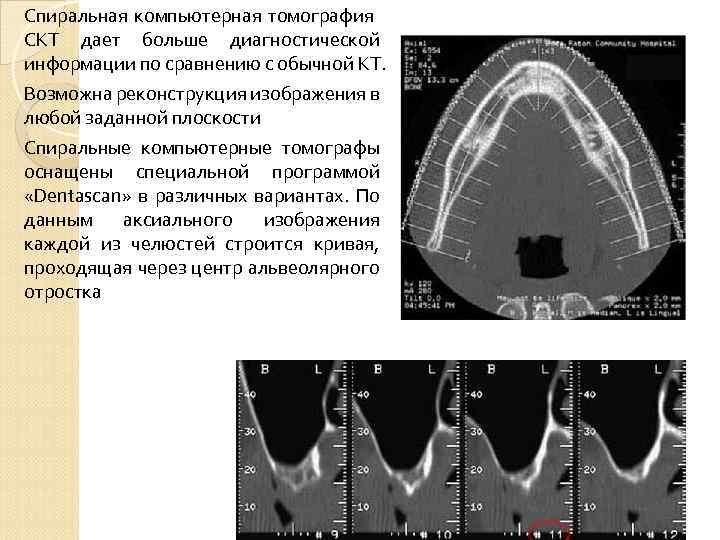

Спиральная компьютерная томография СКТ дает больше диагностической информации по сравнению с обычной КТ. Возможна реконструкция изображения в любой заданной плоскости Спиральные компьютерные томографы оснащены специальной программой «Dentascan» в различных вариантах. По данным аксиального изображения каждой из челюстей строится кривая, проходящая через центр альвеолярного отростка

Спиральная компьютерная томография СКТ дает больше диагностической информации по сравнению с обычной КТ. Возможна реконструкция изображения в любой заданной плоскости Спиральные компьютерные томографы оснащены специальной программой «Dentascan» в различных вариантах. По данным аксиального изображения каждой из челюстей строится кривая, проходящая через центр альвеолярного отростка